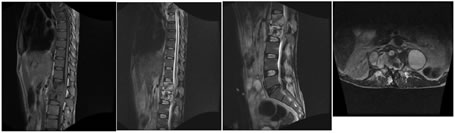

A: SAGITTAL T1W; B: SAGITTAL T2W C: SAGITTAL STIR;

D: AXIAL T1W; E: AXIAL T2W

Figure 1: 28 year male presenting with fever and mid backache. Kyphotic deformity due to collapse of T4 and T5 vertebral bodies with near complete obliteration of T4-T5 intervening disc space (A, B, C). Prevertebral and paravertebral abscess seen extending into epidural space. Significant cord compression noted (D, E)